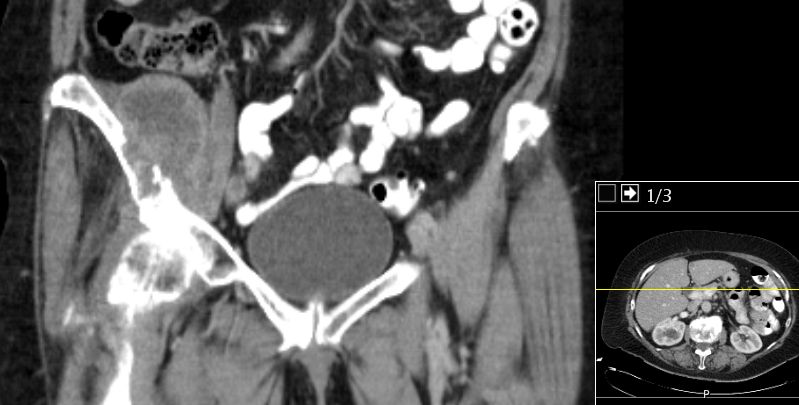

| Fall | 75-jährige Frau mit zunehmenden Schmerzen der rechen Leiste

und Hüfte seit 3 Monaten. ![]() |

CT: 6,4 x 4 cm große kapsulierte tumoröse Raumforderung in der Fossa iliaca rechts mit knöchernen Destruktion des Os

ileum. Dichte bis 20 HEs.![]() |